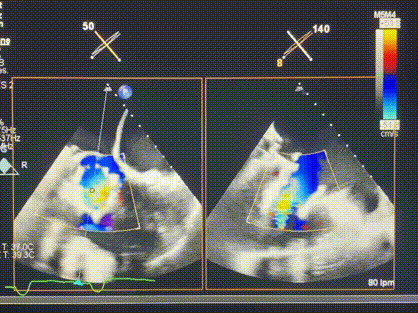

術(shù)后超聲顯示僅殘余微量瓣周漏

LuX-Valve Plus經(jīng)血管三尖瓣置換系統(tǒng)此次“出海”圓滿完成,術(shù)后Rodrigo Estévez-Loureiro教授對LuX-Valve Plus經(jīng)血管三尖瓣置換系統(tǒng)的器械性能和治療效果大為稱贊,認(rèn)為LuX-Valve Plus的手術(shù)體驗非常好。術(shù)后即刻超聲顯示三尖瓣反流幾乎完全消失,血流動力學(xué)改善顯著,患者恢復(fù)快。在面對復(fù)雜解剖結(jié)構(gòu)、超聲影像質(zhì)量不佳、有起搏導(dǎo)線干擾時,Lux-Valve Plus也體現(xiàn)了極強的適應(yīng)性。Thomas Modine教授和Anson Cheung教授也肯定了LuX-Valve Plus術(shù)中操作的便捷性,認(rèn)為LuX-Valve Plus容錯率高,對術(shù)中影像的依賴較小,后期希望可以更多的應(yīng)用LuX-Valve Plus三尖瓣置換系統(tǒng)于臨床實踐,讓更多的三尖瓣重度反流患者盡早獲益,改善預(yù)后。